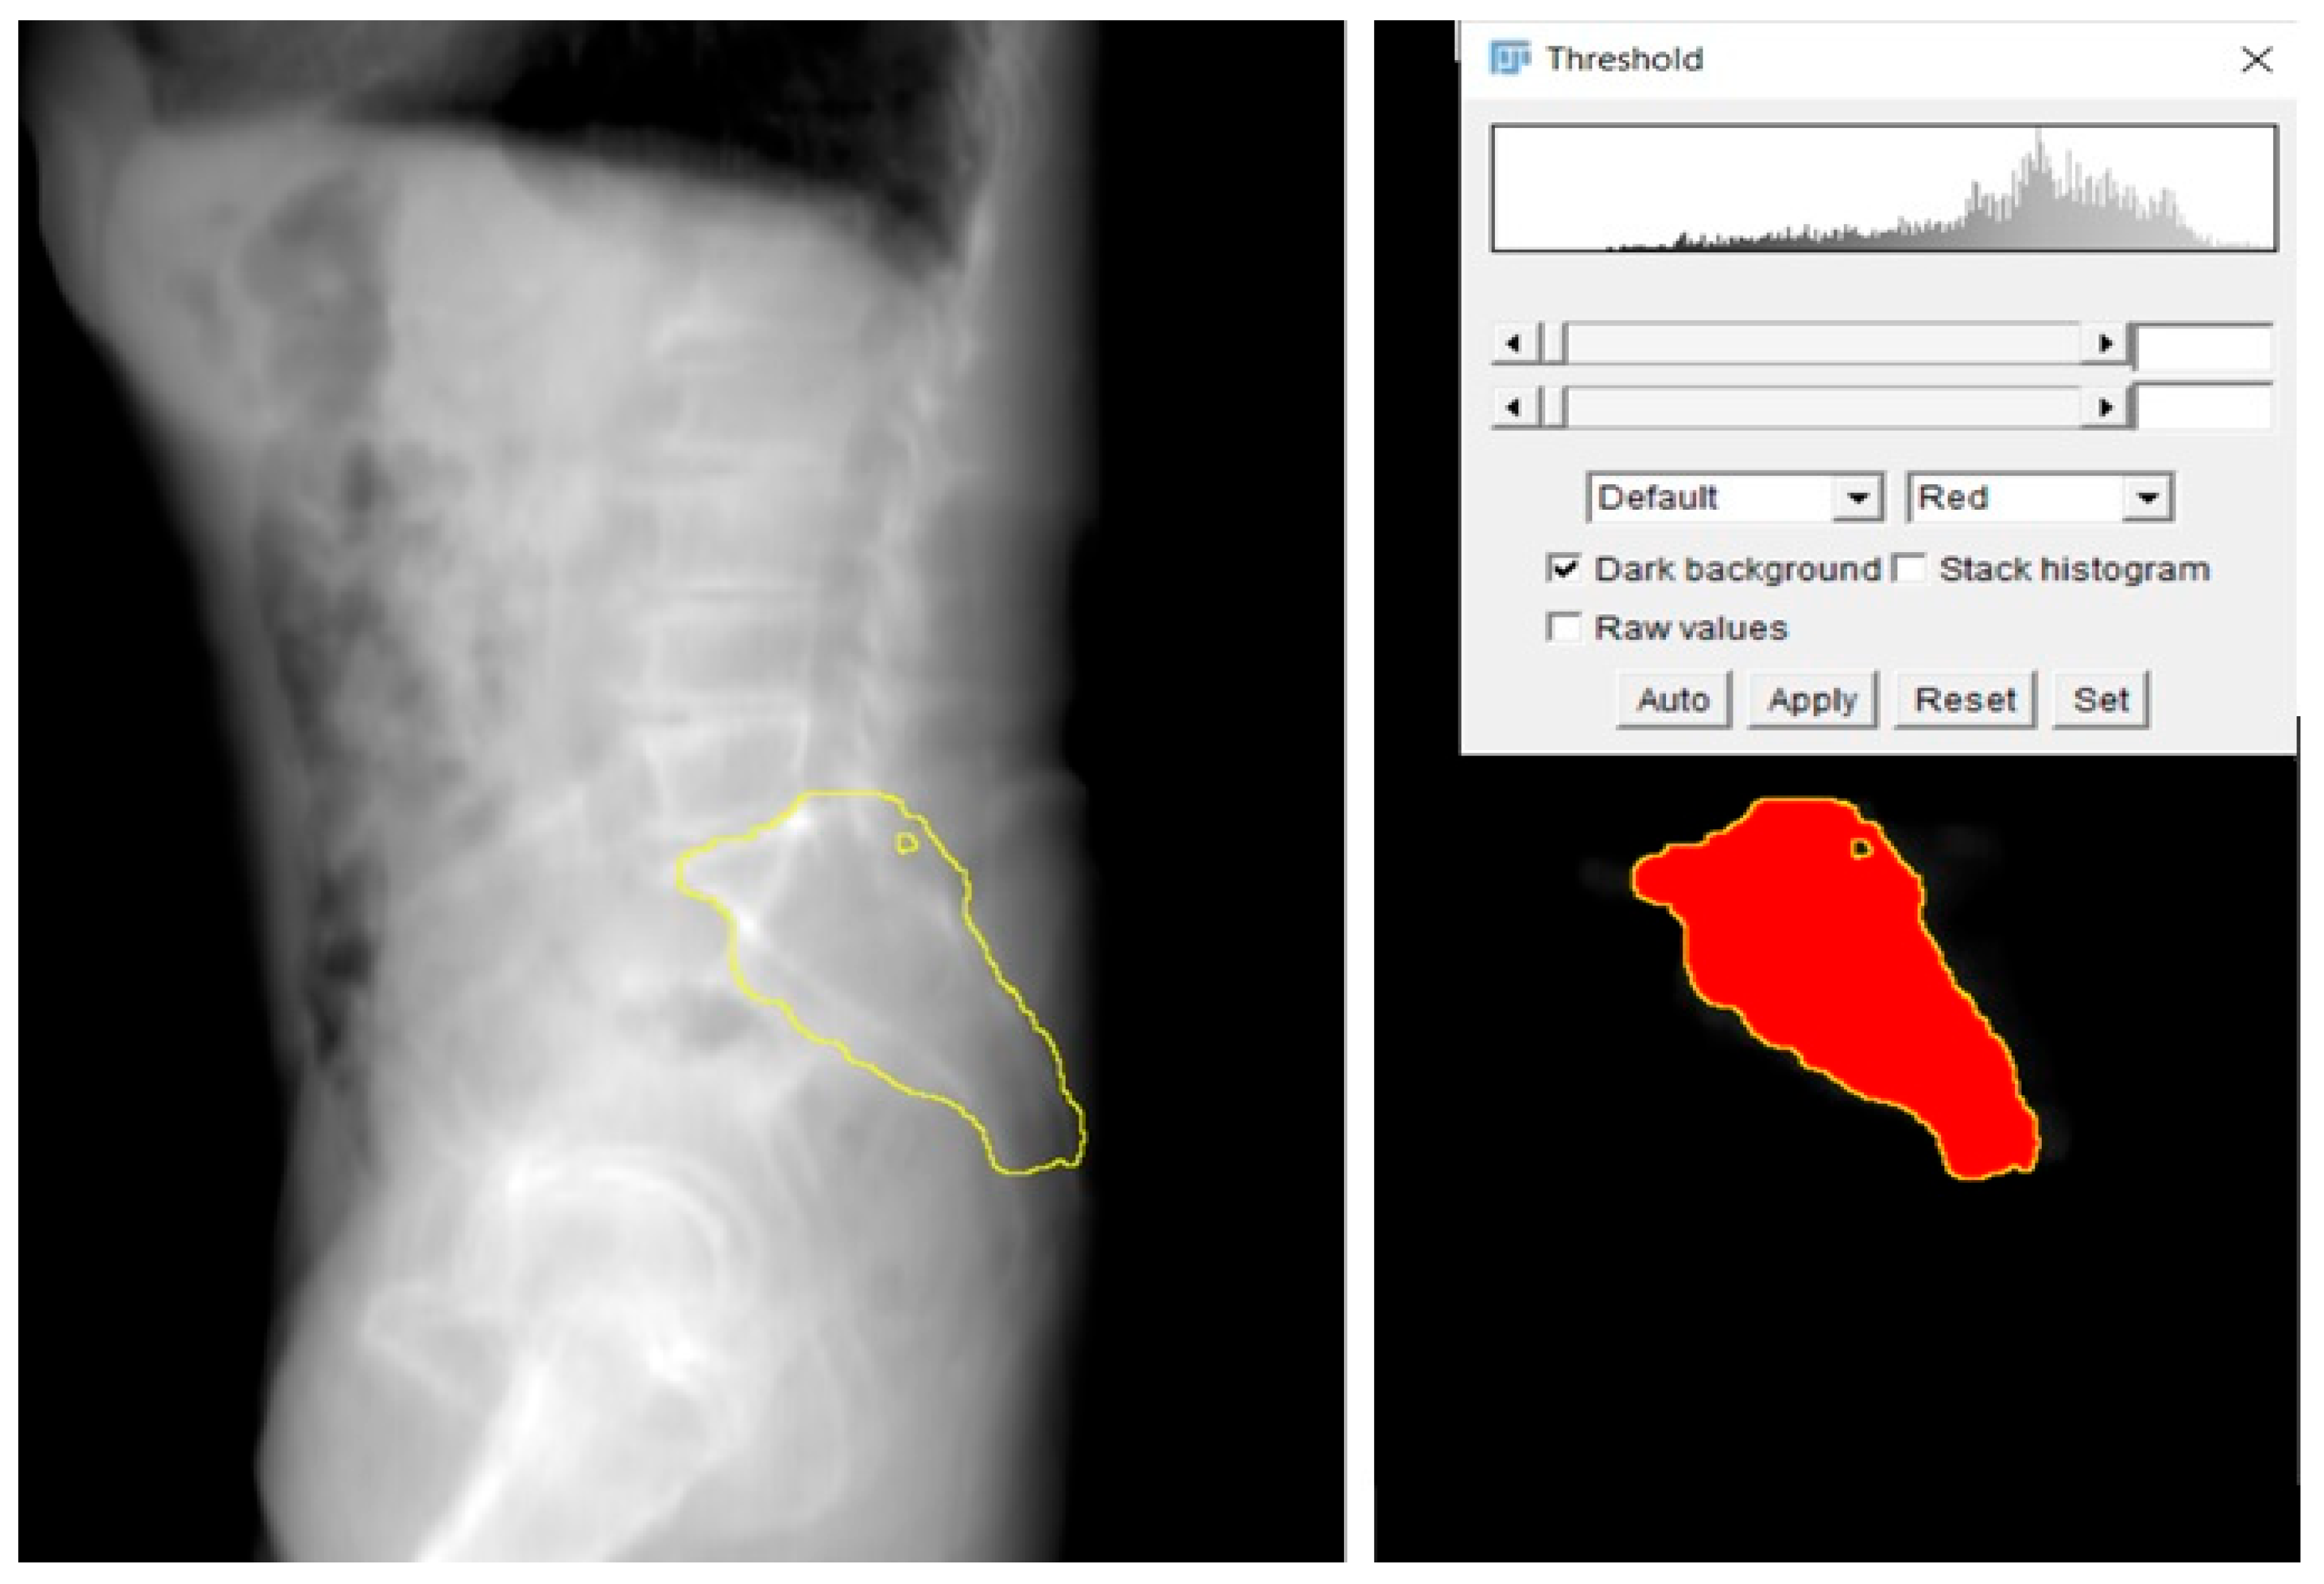

- Manual Segmentation: Initial segmentation of the SI region was performed manually using Avizo software (version 2020.3, Thermo Fisher Scientific, Waltham, MA, USA). Standard thresholding techniques were attempted; however, due to the relatively low bone density in the SI region, these methods were ineffective in accurately delineating the joint.

- Freehand Segmentation: To overcome the limitations posed by the low-density bone structure, a freehand segmentation approach was employed. This method, which involved manually tracing the boundaries of the SI region, took approximately one hour to complete. The result was a high-precision binary mask of the SI region, which was then used to create an accurate 3D model of the joint.

- 2D Projection Creation: From the 3D model, a 2D lateral view of the sacrum was generated by summing the Y-axis slices of the dataset. This 2D projection effectively reflected the bone density distribution within the sacrum and was crucial for visualizing regions of higher bone density. These areas were considered optimal for screw placement, as higher density regions are more likely to provide stable, intraosseous fixation.